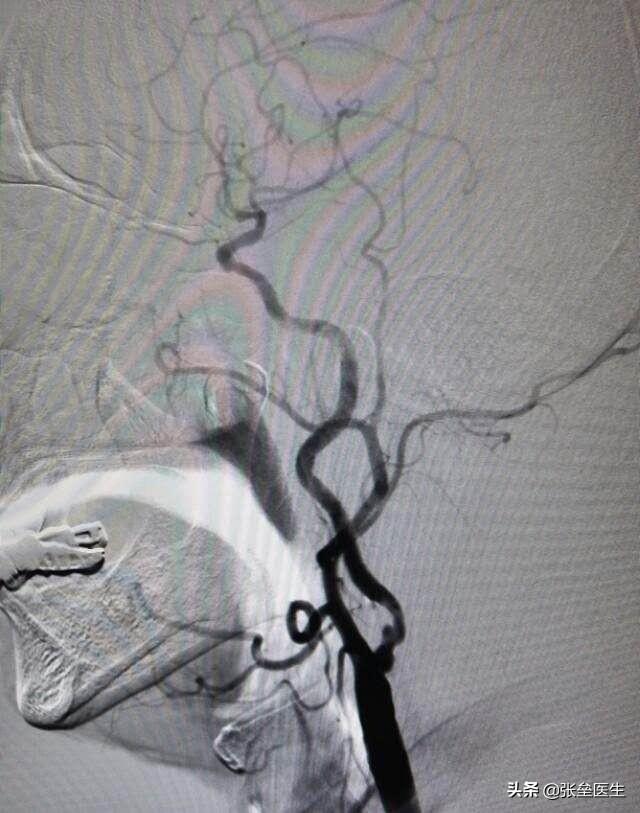

②Il existe également l'angiographie cérébrale, un examen vasculaire invasif qui n'est généralement pas privilégié. Elle repose sur une approche artérielle des branches et des orifices des artères cérébrales, où un cathéter est introduit dans l'artère cérébrale.Il s'agit d'une méthode consistant à injecter un produit de contraste dans les vaisseaux sanguins afin de les rendre visibles aux rayons X, ce qui permet de savoir si les vaisseaux sanguins présentent des sténoses, des plaques ou des malformations.